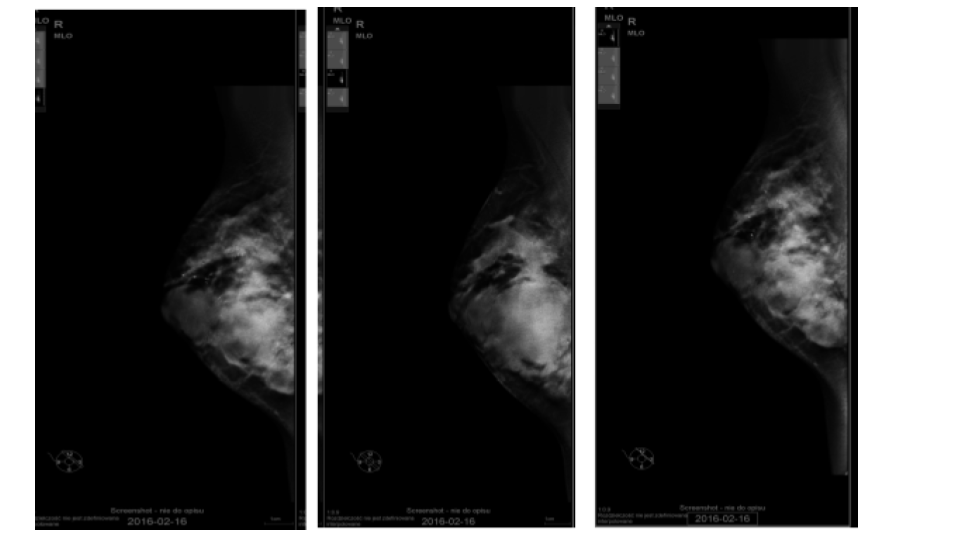

The goal of screening asymptomatic women is to find breast cancer in its earliest stages when treatment has the highest chance for survival. For diagnosis and characterization of primary breast lesions, anatomical imaging such as mammography is the most common screening test for breast cancer, which is basically an x-ray picture of the breast. Examples of mammography images are shown in Fig. 1 for a 67 year old patient. Mammography may find tumors that are too small to feel. It may also find ductal carcinoma in situ (DCIS) [10]. Mammography is more averse to discover breast tumors in women with dense breast tissue. Since both tumors and dense breast tissue seems white on a mammogram, it is hard to find a tumor when there is a dense breast tissue. The mammography sensitivity varies in the range depending on the age of the examined group and number. This range for sensitivity varies from 80% to 96% and in case of specificity it is in the range of 15 to 51.8% [11].